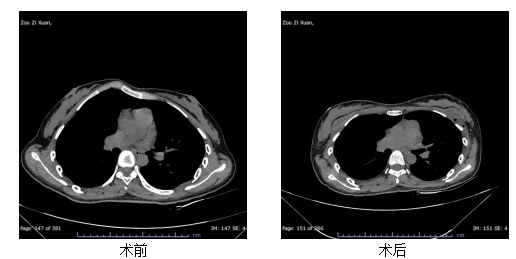

近日,湖北省第三人民医院(湖北省中山医院)胸外科(血管外科)收治了一位18岁的鸡胸患者。该患者因胸骨明显前凸,不仅运动时感到呼吸受限,更因外观问题长期承受着巨大的心理压力。科室团队为其成功实施了胸骨沉降手术,术后患者胸廓外观改善明显,呼吸功能有效恢复,困扰多年的心理负担也终于得以卸下。

畸胸并非无法解决。对于3~10岁轻度畸形,可使用胸廓负压吸引装置(漏斗胸)或胸部支具(鸡胸),配合扩胸运动等康复训练,多数可改善。严重畸形或保守治疗无效者则需手术。漏斗胸常用Nuss手术,通过胸腔镜植入弧形钢板撑起胸骨;鸡胸则多采用胸骨沉降术调整胸肋位置。最佳手术年龄为6~12岁,此时胸壁柔韧性好,恢复快,术后效果更稳定。